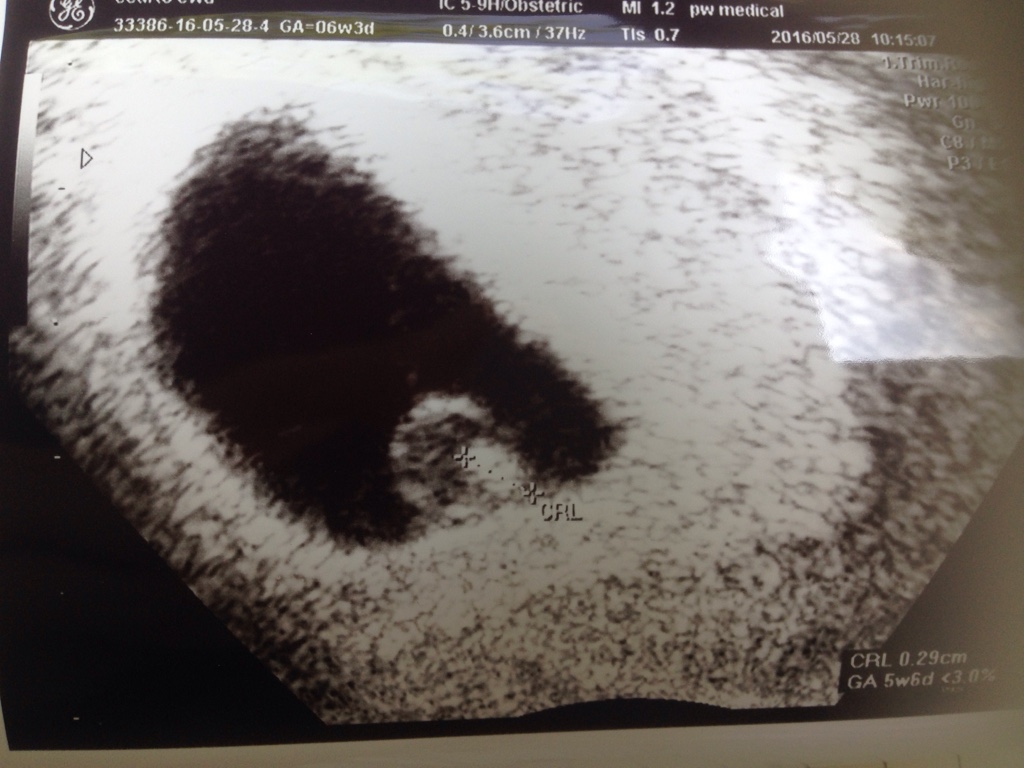

My juz po USG! :)

Z dzidziusiem wszystko dobrze, uslyszelismy serduszko!!!!!!!! [emoji7][emoji7][emoji7] cos niesamowitego!

A tutaj na dole liniaz zapisem tetna [emoji7]